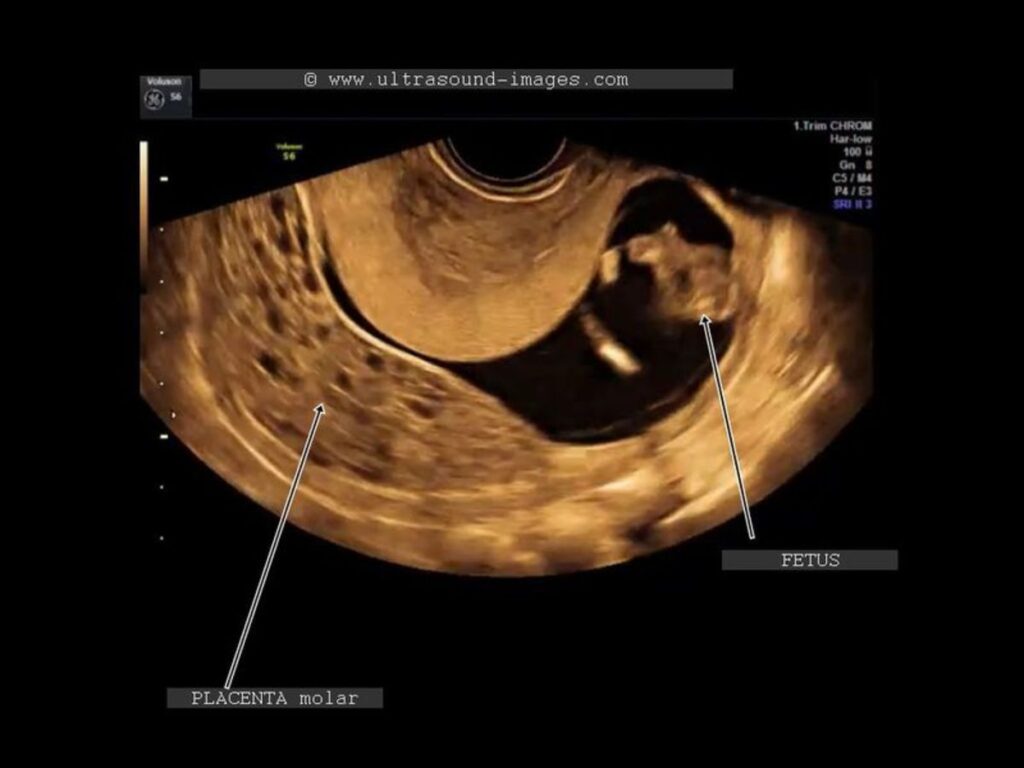

Existen dos tipos de mola hidatiforme: la completa y la parcial. Hablamos de embarazo molar completo cuando el tejido fetal no llega a desarrollarse en ningún grado y la placenta se encuentra inflamada, tiene un aspecto poco habitual y forma quistes llenos de líquido. En los casos de mola completa en ocasiones ni siquiera se forma la placenta.

Por contra, en la mola hidatiforme parcial es posible observar tejidos placentarios normales, si bien combinados con otros de naturaleza patológica. De hecho puede que incluso se forme parcialmente el feto, si bien éste no podrá sobrevivir a la gestación y lo más probable es que sea expulsado por el organismo de la madre por medio de un aborto espontáneo durante el primer trimestre del embarazo.